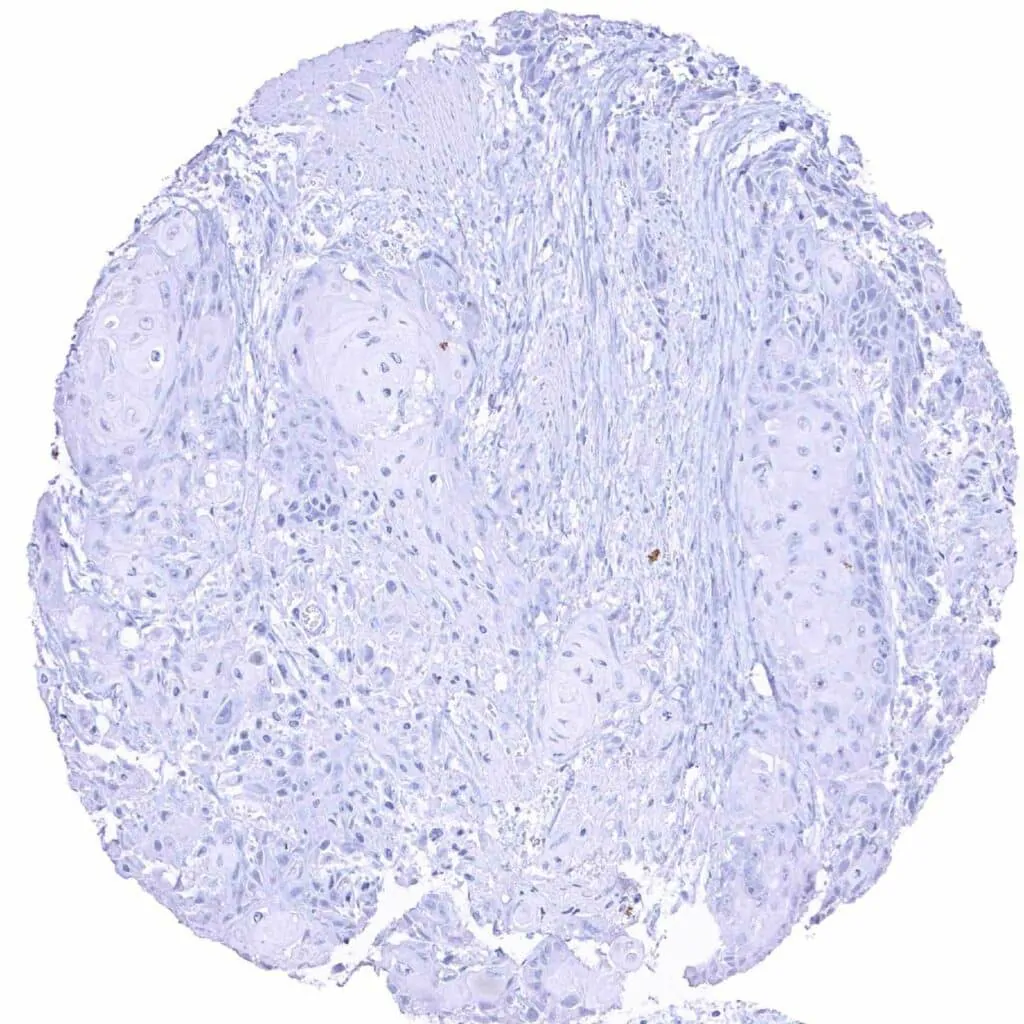

Breast – MYH7 negative invasive breast cancer of no special type (NST)